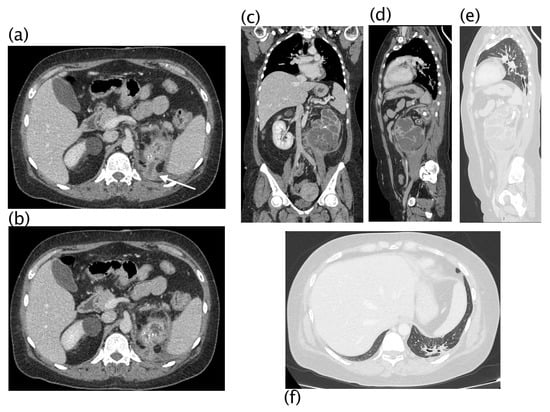

Figure 6.

Xanthogranulomatous pyelonephritis Stage III—pararenal form CT with contrast agent: axial (a,b,e), coronal (c), and sagittal (d) MPR reconstructions with lung window (e,f). Patient admitted for persistent cough and left basal opacity on chest X-ray examination. On CT examination, morpho-structural alteration of the kidney with gross intraparenchymal collections alternating with dilated calyces is present. An upper polar fistulous via (a,b) is well evident (white arrow) that continues into the lung in direct continuity with a bronchus, more evident in sagittal reconstructions. Recognition of the fistulous via on CT was visible in 22.22% of patients.